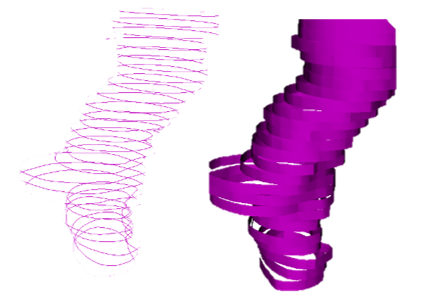

图像分割(也称为轮廓绘制或注释)是一种在图像中划定区域的程序,通常对应于解剖结构、病变和各种其他对象空间。它是医学图像计算中非常常见的程序,因为它是可视化某些结构、定量分析(测量体积、表面、形状属性)、3D打印和遮罩(将处理或分析限制在特定区域)等所必需的。

分割可以手动进行,例如通过遍历图像的所有切片并在边界处绘制轮廓;但通常使用半自动或全自动方法。Segment Editor模块提供了多种分割方法。

分割的结果存储在3D Slicer中的segmentation节点中。一个分割节点由多个段组成。

一个段指定单个结构的区域。每个段都有许多属性,如名称、首选显示颜色、内容描述(能够存储标准DICOM编码条目)和自定义属性。段可以在空间上相互重叠。

一个区域可以用不同的方式表示,例如作为二进制标签图(每个体素的值指定该体素是在区域内还是区域外)或闭合表面(表面网格定义区域的边界)。没有一种表示方式适用于所有情况:每种表示方式都有其优缺点,并根据需要使用。

每个段存储在多个表示中。一个表示被指定为源表示(在用户界面上标有“金星”)。源表示是唯一可编辑的表示,它是保存到文件时唯一存储的表示,所有其他表示都是从它自动计算的。

二进制标签图表示

二进制标签图表示可能是最常用的表示,因为这种表示最容易编辑。使用这种表示的大多数软件将所有段存储在一个3D数组中,因此每个体素只能属于一个段:段不能重叠。在3D Slicer中,允许段之间的重叠。为了在二进制标签图中存储重叠的段,段被组织成层。每个层在内部存储为一个单独的3D体积,一个体积可以在许多不重叠的段之间共享以节省内存。

在源表示设置为二进制标签图的分割中,每个层暂时允许具有不同的几何形状(原点、间距、轴方向、范围) - 以允许在分割之间移动段而不会产生不必要的质量损失(每次对二进制标签图进行重采样都会导致轻微变化)。在某些编辑操作和分割保存到文件时,所有层被强制具有相同的几何形状。